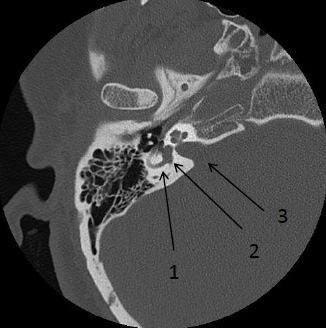

Identify the labeled structures: